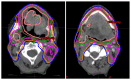

Radiation recall dermatitis is an inflammatory reaction of the skin that may infrequently occur in areas of the skin that have been previously treated with radiation therapy. This is thought to be due to a triggering agent administered after radiation therapy which leads to an acute inflammatory reaction, manifesting as a skin rash. We present the case of a 58-year-old male with recurrent invasive squamous cell carcinoma of the tongue, previously treated with chemotherapy and radiation therapy, who presented with progression of his disease. He was treated with pembrolizumab and subsequently developed a new-onset facial rash over the previously treated radiation field. The distribution of the rash was suggestive of radiation recall dermatitis. A biopsy showed dermal necrosis without evidence of dermatitis, vasculitis, or infectious process. This case highlights the incidence of a rare complication of immune checkpoint inhibitor therapy and emphasizes the need for careful monitoring for radiation recall dermatitis.